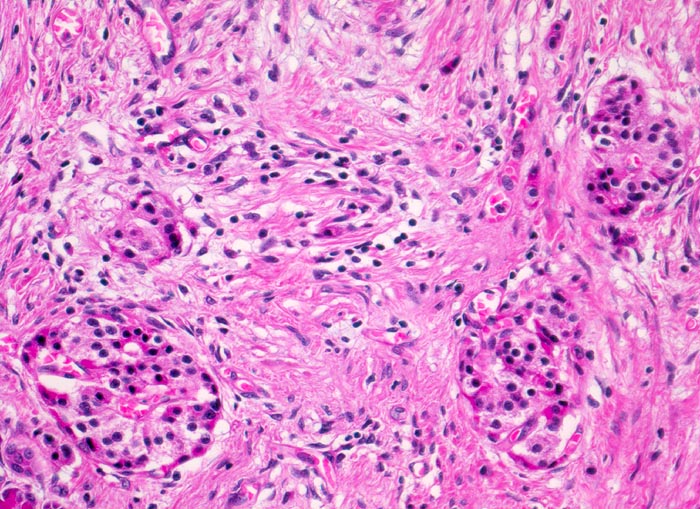

Chronisch-sklerosierende Pankreatitis

Während die Azini das exokrine Pankreasparenchym zunehmend fibrosieren und schliesslich ganz verschwinden, bleibt das endokrine Pankreas relativ gut erhalten. Nach Verschwinden der Azini sind im fibrosierten Gewebe Pankreasinseln zurückgeblieben. Geringgradiges lymphoplasmazelluläres Entzündungsinfiltrat.

Durch das Verschwinden des exokrinen Pankreas rücken die Inseln näher zueinander und erscheinen zahlreicher als normal. Dies führt zum fälschlichen Eindruck einer Hyperplasie der Pankreasinseln.